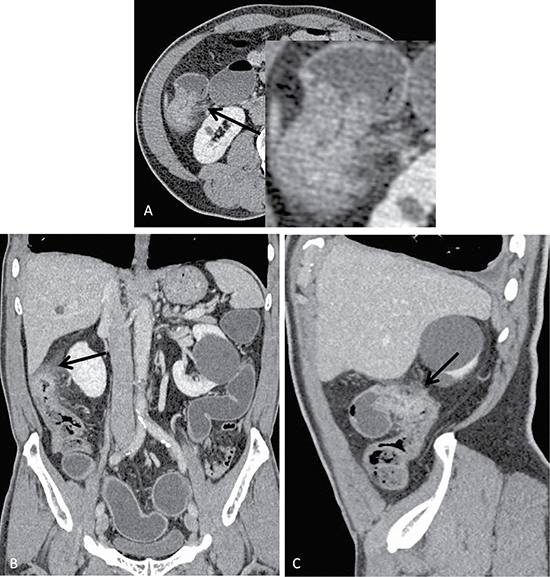

The results of the model-predicted colorectal cancer T-staging were highly consistent with the results of the pathological gold standard and much more accurate than traditional methods (Table 3). The model correctly predicted the T-stage of the validation cohort for 167 of 192 (86.98%) patients, whereas the traditional method correctly predicted the T-stage for only 98 patients (51.04%), this difference was significant (χ2 = 57.974, p < 0.001). Moreover, the prediction of the model for ≤ T2 and T3 disease was more accurate than that of the traditional method (χ2 = 24.738, 39.6; p < 0.001, < 0.001), there is no statistical differences for T4 disease (χ2 = 3.316, p = 0.069). The model incorrectly overestimated and underestimated the stage for 17 of 25 patients (68%) and 8 patients (32%), respectively. Specifically, 10 patients with ≤ T2 disease were predicted to have stage T3 disease, and 7 patients with stage T3 disease were predicted to have T4 disease. Conversely, 5 patients with stage T3 disease were predicted to have ≤ T2 disease, and 3 patients with T4 disease were predicted to have T3 disease. Using the traditional method, the staging was incorrectly overestimated and underestimated for 81 of 94 patients (86.17%) and 13 patients (13.83%), respectively. Figure 1 shows a pathologically confirmed T3 colorectal cancer lesion that was misdiagnosed as a T4 lesion by traditional method because the tumor exhibited a strip-like, high-density appearance in the peripheral adipose tissue. The model classified this lesion as T3 stage correctly. Thus the opacity of the tumor surrounding fat is not a tumor infiltration, but an inflammatory response.

Figure 1: Axial (A), coronal (B) and sagittal (C) images of a colon cancer lesion located in the hepatic flexure of the colon of a 72-year-old male who presented with a change in defecation habits. Conventional methods preoperatively predicted the T-stage as T4 because of evident serosa thickening, increased surrounding fat gap density, a blurred neighboring peritoneal border, and adjacent peritoneal thickening on the CT image. Conversely, the model predicted T3 disease, which was consistent with the pathological staging.